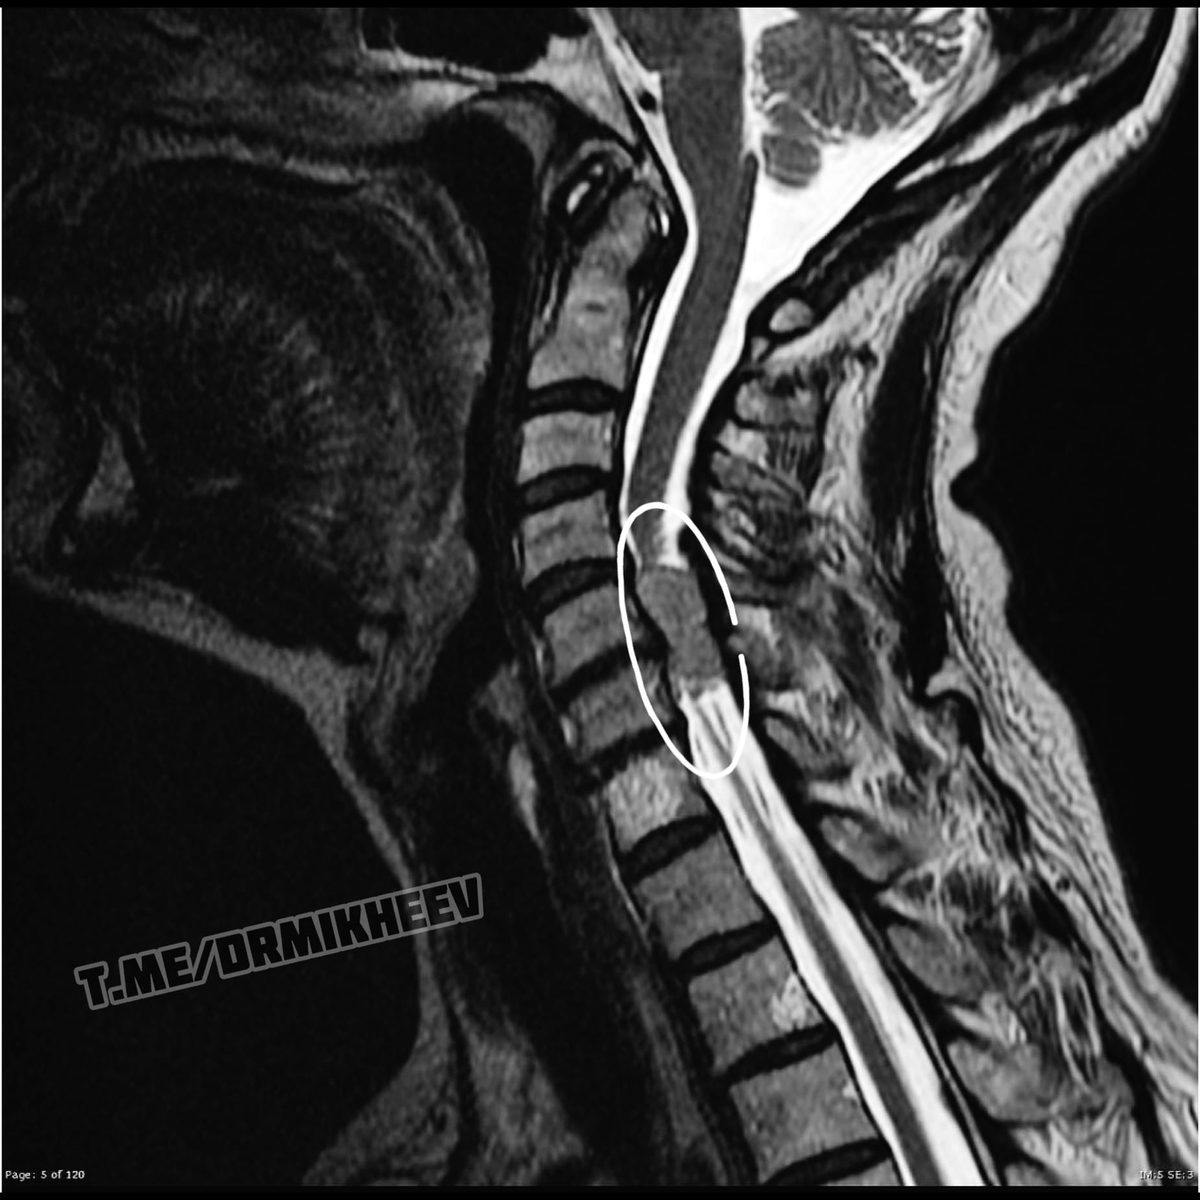

НЕВРИНОМА (шваннома)

Сегодня хочу показать пример того, почему не стоит пренебрегать МРТ, если Вам об этом говорят. Есть такая «штука», которая называется НЕВРИНОМА, или ещё как называют ШВАННОМА☝🏻 Второе название получено, потому что развивается она из шванновских клеток🌀 Это доброкачественная опухоль и развивается она достаточно медленно и долгое время не даёт о себе знать.

Вообще чаще всего ее диагностируют в шейном или грудном отделе, реже в поясничном. Рассмотрим симптоматику грудного и шейного отдела.

На фото приведены пара примеров МРТ. #ДокторМихеев